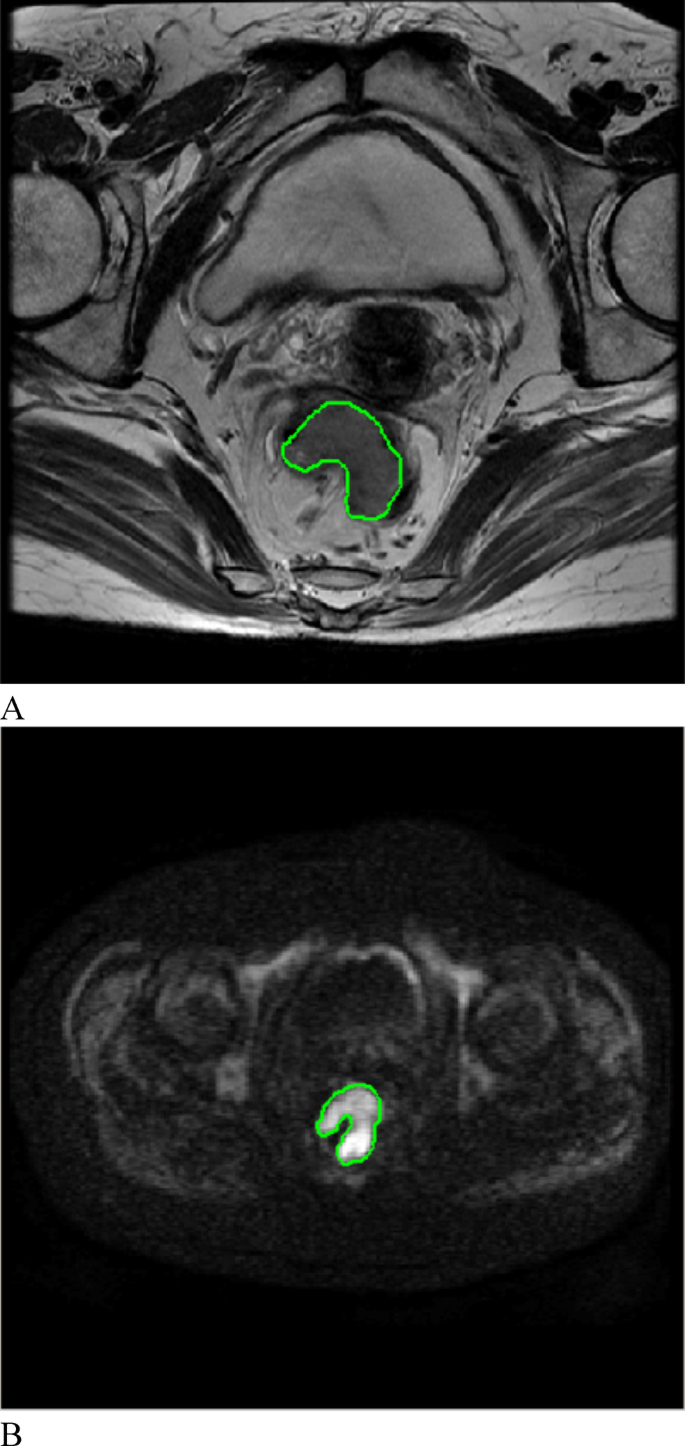

All MR images of the 194 patients with CRC were retrieved in DICOM format from the Picture Archiving and Communication Systems (PACSs). To minimize the impact of different MRI scanners and acquisition parameters on the radiomic analysis, all the images were preprocessed before feature extraction. Preprocessing included resampling to an isotropic voxel size of 3.0 × 3.0 × 3.0 mm3, gray-level discretization with a fixed bin width of 25, and gray-level normalization to standardize the voxel intensities across patients30,31. The preprocessed MR images were subsequently imported into IBEX software (β1.0, http://bit.ly/IBEXMDAnderson) in DICOM format for segmentation of the tumor lesions. Radiologist A (Yao-Kun Wu), with 2 years of work experience, delineated each lesion layer by layer on (oblique) axial T2W and DW images to generate a volume of interest (VOI) (Fig. 2). Gas in the intestinal lumen, cystic degeneration between the lesion and the normal bowel, necrotic and transitional areas and adipose tissue around the intestinal wall were avoided. The operator was not aware of the basic information of the patient, such as the clinical and pathological results, before the target volume was delineated. Finally, the radiomic features were extracted, and the T2WI and DWI feature datasets were generated.

On oblique axial T2WI and DWI, the ROI was manually delineated layer by layer along the edge of the rectal cancer lesion. (A) T2-weighted imaging; (B) diffusion-weighted imaging.